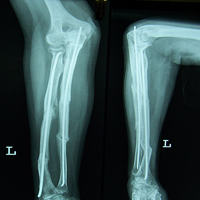

Case:6 Segmental Comminuted Fracture Radius

Patient, aged 75 years during morning walk tripped & had a fall following which he sustained injury to the left forearm. Closed reduction & interval fixation with Intra-medullary TEN nails was done in radius & ulna. Now he has full supination & pronation function of forearm.

Pre-Op

Post-Op